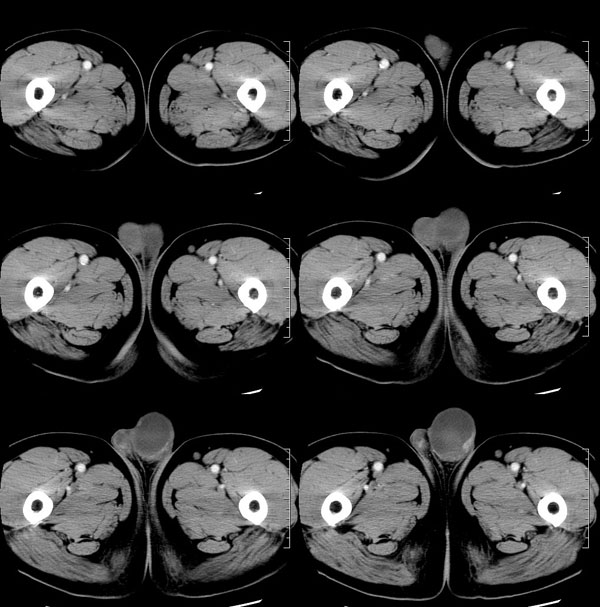

| 男性,69岁。自2个月前开始无意中发现左侧阴囊内一鸡蛋大小肿物,当时无伴疼痛等不适,未予重视。肿物逐渐增大,近段时间常伴左会阴部、腹股沟区牵扯不适,并于2周前在我院门诊行彩超检查提示“左侧附睾肿瘤可能,左侧睾丸鞘膜积液”。 专科检查:左侧阴囊肿大,其内可触及一鹅蛋大小肿物,表面光滑。肿物前部呈囊性感,后部质硬,按压无疼痛,无缩小,活动度良好。左侧睾丸未触及,透光试验(±)。                 王仕学发言:左侧睾丸见一密度不均肿块,边缘清楚,周围见水样密度影;考虑睾丸生殖细胞性肿瘤可能性大. 睾丸肿瘤占生殖系统肿瘤的3%-5%,占男性恶性肿瘤的0.5%-1.0%,其中生殖细胞性肿瘤占95%.睾丸肿瘤包括生殖细胞和非生殖细胞肿瘤两大类,前者占95%以上,后者不到5%.非生殖细胞肿瘤虽少见,但种类繁杂,主要有支持细胞、间质细胞和支持细胞-间质细胞瘤等功能性肿瘤,和间皮瘤、腺癌、横纹肌肉瘤、粘液性囊腺瘤、纤维上皮瘤、黑素神经外胚瘤、淋巴瘤等附属组织肿瘤。不同的病理类型的睾丸肿瘤发病率高峰不同,睾丸癌多发于35岁以前,精原细胞瘤发病高峰为30-35岁。精原细胞瘤约占睾丸肿瘤的60%,发病高峰在30-35岁。85%的患者睾丸有明显肿大,肿瘤局部侵犯力较低,肿瘤一般有明显界限。 手术:行“左侧附睾、睾丸、精索切除术”。 病理诊断:(左睾丸、附睾)肿物,为低分化腺癌。另送检(左精索远端)肿物,镜下亦为低分化腺癌。 免疫组化:ck(l)(++++)、cea(+++)、ca19-9(-)、psa(-)、plap(-)、p53(-)、vimentin(-)。 原贴地址:http://www.radinet.com.cn/forum_view.asp?forum_id=4&view_id=30707 |